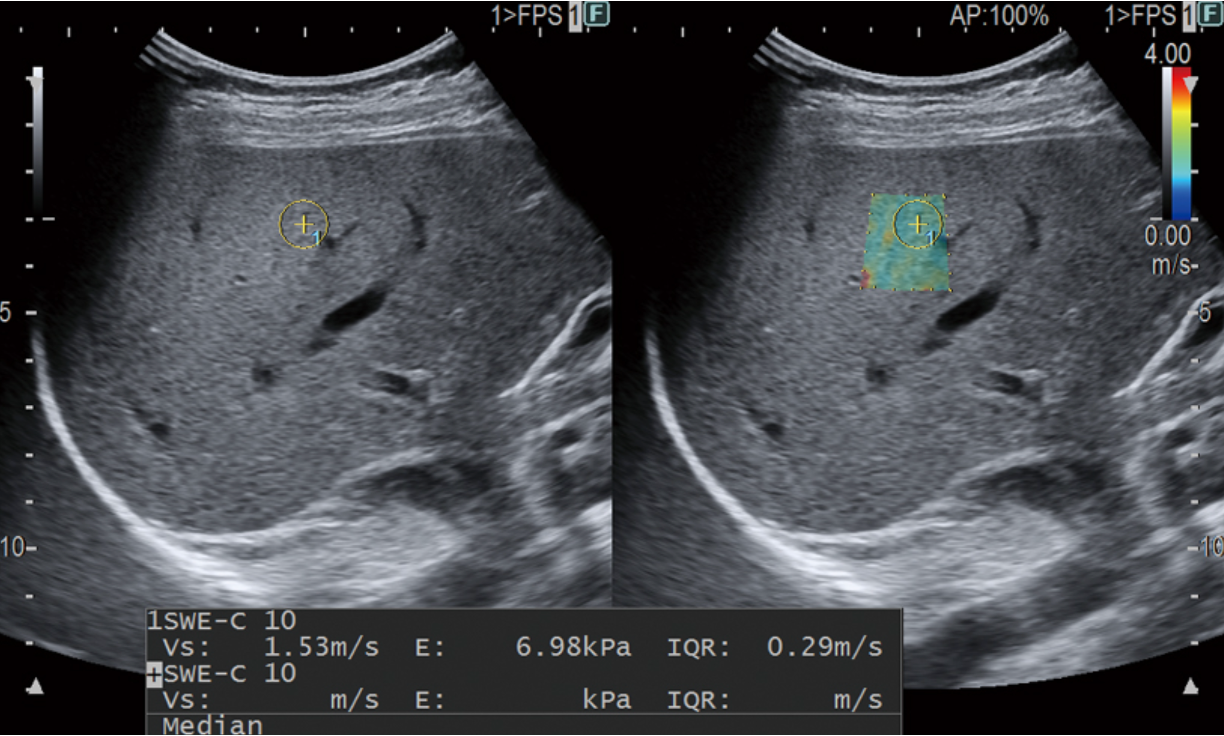

Da jeder Eingriff in den menschlichen Körper ein Blutungs- und Infektionsrisiko birgt, suchte man seit langem nach einer alternativen Methode, um die Steifigkeit der Leber zu bestimmen. Die Scherwellen-Elastographie (SWE) ist ein Ultraschallverfahren, das es erlaubt, das Ausmaß einer Leberschädigung zuverlässig auf nicht invasive Weise abzuschätzen. Es dient der Diagnose und Verlaufskontrolle bei Lebervernarbungen (Fibrose) bzw. Leberschrumpfung (Zirrhose).

Bei der Untersuchung wird die Leberelastizität als Maß für die Verformbarkeit des Lebergewebes bestimmt. Je fester und unelastischer das Lebergewebe ist, desto schneller laufen die Ultraschallwellen hindurch und verformen das Gewebe. Auf diese Weise kann der Bindegewebsumbau der Leber in hoher Übereinstimmung mit der ansonsten invasiv durchzuführenden Leberbiopsie dargestellt werden. Das Verfahren eignet sich, um den Erfolg einer medikamentösen Therapie im Verlauf zu dokumentieren.

Durch die Integration der beiden nicht-invasiven Methoden zur Beurteilung von Lebergewebe Steifigkeit (RTE und SWM), ist eine chronologische Beurteilung möglich um das Fortschreiten von Leberentzündungen und -fibrosen mit größerer Genauigkeit zu beurteilen als bisher.